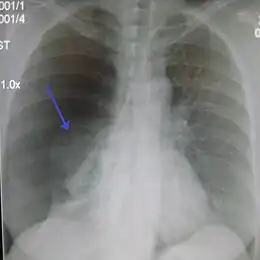

La radiographie du thorax de face permet de faire, en règle générale, le diagnostic, sous forme d'une clarté d'un sommet (ou péri hilaire dans les cas plus important) avec visualisation d'un fin liseré convexe vers le haut, correspondant au poumon rétracté. Dans les cas difficiles, on peut s'aider d'une radiographie prise en expiration. La présence simultanée d'un épanchement liquidien donne l'aspect de niveau hydro-aérique rectiligne horizontal caractéristique.